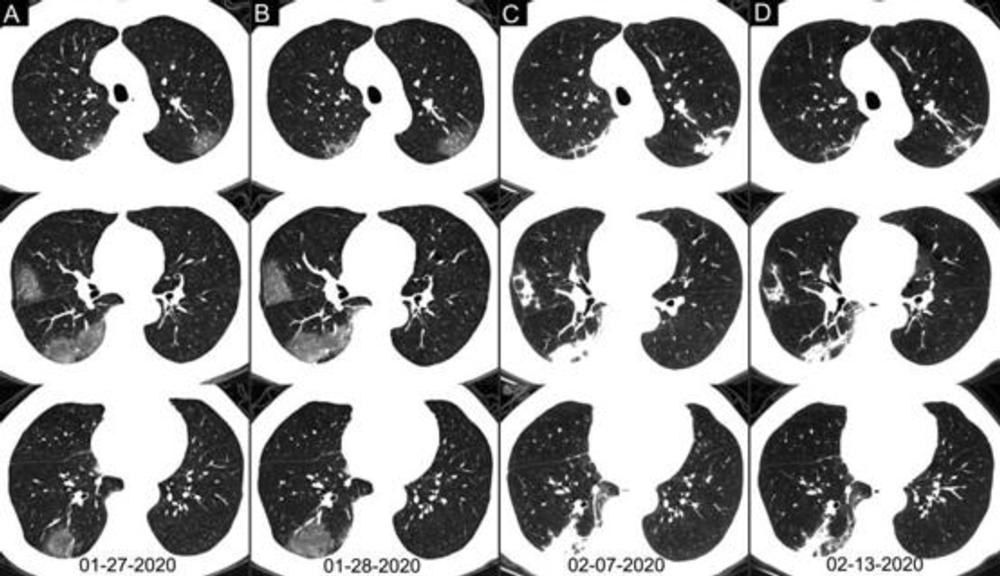

Figure 5. Chest CT images of a 62-year-old man with fever for 2 weeks, and dyspnea for 1 day. Negative results of RT-PCR assay for the SARS-CoV-2 using a swab samples were obtained on February 3 and 11, 2020, respectively. (A) Chest CT with multiple axial images shows multiple ground-glass opacities in the bilateral lungs. (B) Chest CT with multiple axial images shows enlarged multiple ground-glass opacities. (C) Chest CT with multiple axial images shows the progression of the disease from ground-glass opacities to multifocal organizing consolidation. (D) chest CT with multiple axial images shows partial absorption of the organizing consolidation.